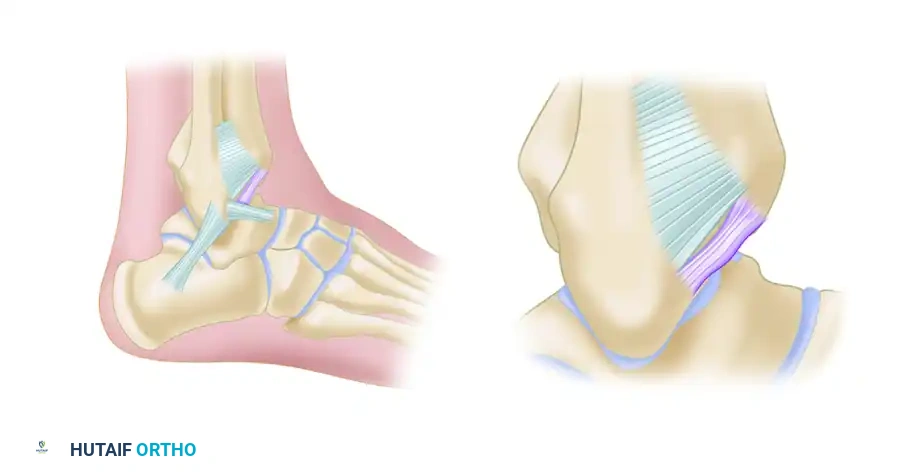

Impingement is not exclusively a bony phenomenon. Chronic anterolateral ankle pain is frequently driven by soft tissue pathology. Following inversion ankle sprains, chronic synovitis, or nondisplaced fractures, hypertrophic scar tissue can accumulate in the anterolateral gutter.

Bassett et al. identified that thickened distal fascicles of the anterior inferior tibiofibular ligament (AITFL) can act as a primary source of impingement. This accessory fascicle, present in the majority of human ankles, runs parallel and distal to the primary AITFL, separated by a fibrofatty septum. During dorsiflexion, this thickened band can impinge on the anterolateral aspect of the talus, causing localized chondromalacia and severe pain.